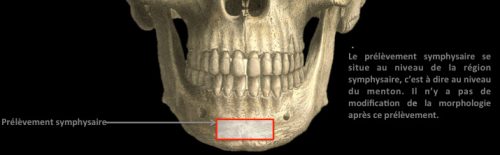

L’intervention chirurgicale consiste en une reconstruction osseuse du maxillaire ou de la mandibule avant la mise en place des implants dentaires par votre chirurgien.